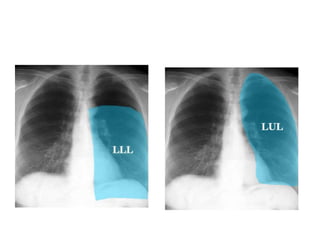

LUL consolidation

Left lower lobe consolidation